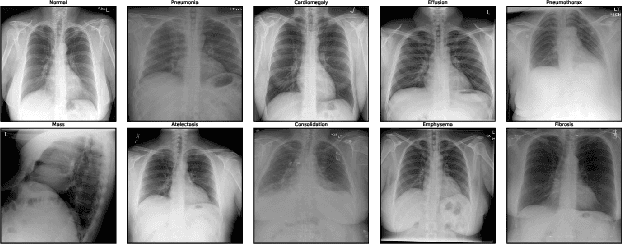

With the rapid progress of large language models (LLMs), advanced multimodal large language models (MLLMs) have demonstrated impressive zero-shot capabilities on vision-language tasks. In the biomedical domain, however, even state-of-the-art MLLMs struggle with basic Medical Decision Making (MDM) tasks. We investigate this limitation using two challenging datasets: (1) three-stage Alzheimer's disease (AD) classification (normal, mild cognitive impairment, dementia), where category differences are visually subtle, and (2) MIMIC-CXR chest radiograph classification with 14 non-mutually exclusive conditions. Our empirical study shows that text-only reasoning consistently outperforms vision-only or vision-text settings, with multimodal inputs often performing worse than text alone. To mitigate this, we explore three strategies: (1) in-context learning with reason-annotated exemplars, (2) vision captioning followed by text-only inference, and (3) few-shot fine-tuning of the vision tower with classification supervision. These findings reveal that current MLLMs lack grounded visual understanding and point to promising directions for improving multimodal decision making in healthcare.